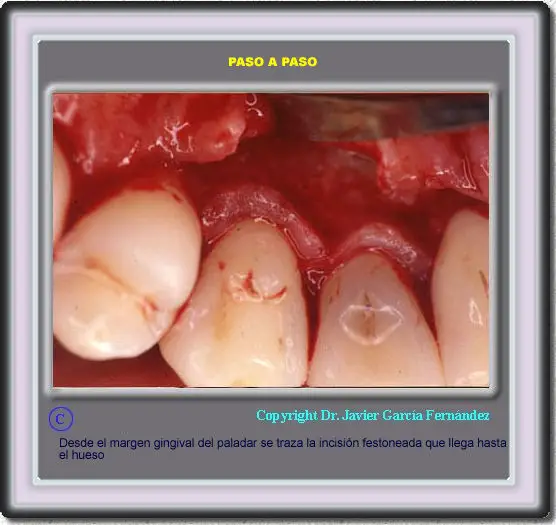

Atlas of Surgical Techniques in Periodontics. Chapter III. Atlas de Técnicas Quirúrgicas en Periodoncia